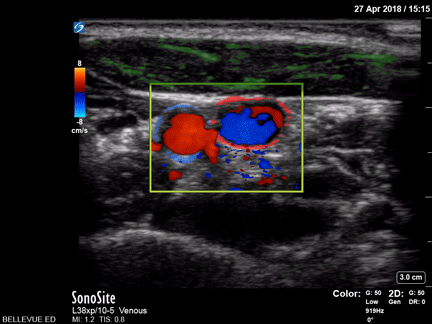

Carotid Artery and Internal Jugular Doppler Green: Sternocleidomastoid, Blue outline: Common carotid artery, Red outline: Internal jugular vein Images: Dr. Lindsay Davis, Dr. Hannah Kopinski. Image Editing: Michael Amador and Dr. Matthew Riscinti